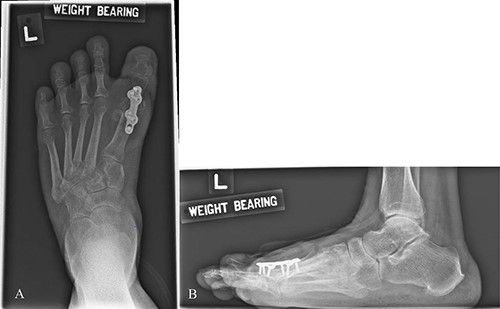

Mdm. S.N.C is a 59-year-old lady with a background of hypertension and diabetes mellitus who had corrective surgery for her left hallux valgus deformity in July 2020 (Fig. 1). This was complicated by wound dehiscence and exposure of the underlying tendon (Extensor hallucis longus) and implant (Fig. 2). An arterial duplex scan was done, which showed 70–80% occlusive disease over the proximal anterior tibial artery (ATA; Fig. 3) that likely contributed to her poor wound healing.

Illustrated diagram of left lower limb arterial duplex scan showing 70–80% occlusive disease at the proximal ATA.

Left lower limb diagnostic angiogram showing occlusion of the ATA with poor flow (arrow).